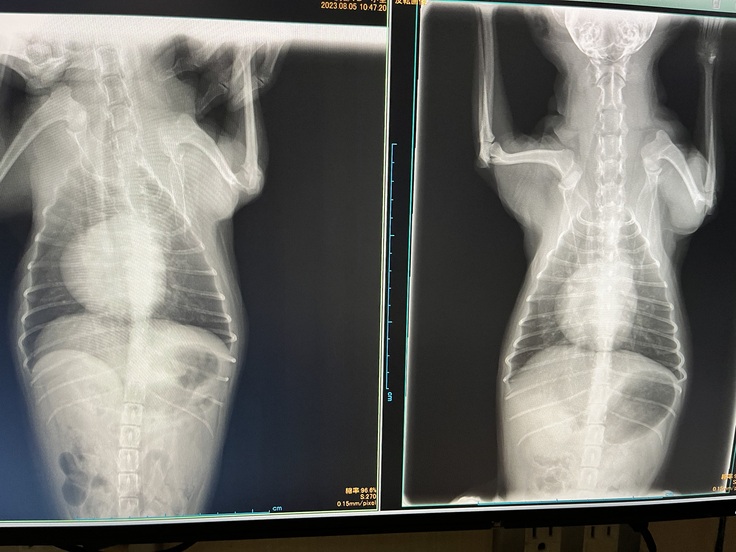

〔7月29日 肺水腫を起こしているレントゲン〕

左7月29日心臓が大きくなっている状態

右8月5日獣医師による処置により改善